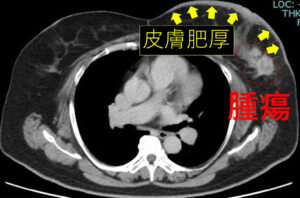

他院、初診時のCT

皮膚肥厚を伴う大きな腫瘍

リンパ節転移も腋窩(Ⅰ+Ⅱ)鎖骨下(Ⅲ)

両方に著明

前医で「手術不能乳癌、薬物療法しかできない」と、言われ当院を受診

皮膚肥厚(つまり皮膚浮腫)が胸全体なので現時点では「手術不能」と言えるけど、それほどでもない。

術前抗がん剤後 腫瘍著明に改善 皮膚浮腫の範囲も縮小

リンパ節も、かなり効いています。